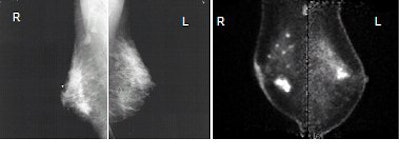

| Images of 50-year-old woman with bilateral breast masses, mammography on the left and PEM on the right. X-ray-guided biopsy showed invasive cancer in right breast, papilloma in the left breast. PEM findings: Left breast very suspicious for cancer. Surgery revealed DCIS. Images courtesy Dr. William Stein and Dr. Marybeth Lobrano, PET Fusion Center, East Jefferson General Hospital, Metairie, LA. |

The group found 48 tumors in the 77 patients, with the PEM system detecting 10 of the 11 cases of pure DCIS, for a sensitivity of 91%. Narayanan said this compares to a sensitivity of 56% for conventional imaging, which she interpreted to be an aggregate of mammography, breast ultrasound, and clinical breast examination. PEM also detected four incidental lesions, picked up in addition to the original confirmed or suspicious lesion that had been detected on mammography.

PEM saw three cases of DCIS foci that were occult on mammography, and one case was missed by all modalities and was discovered only after prophylactic mastectomy. PEM was also able to determine an intraductal component to DCIS in 70% of cases, compared to only 40% for mammography, Narayanan said.